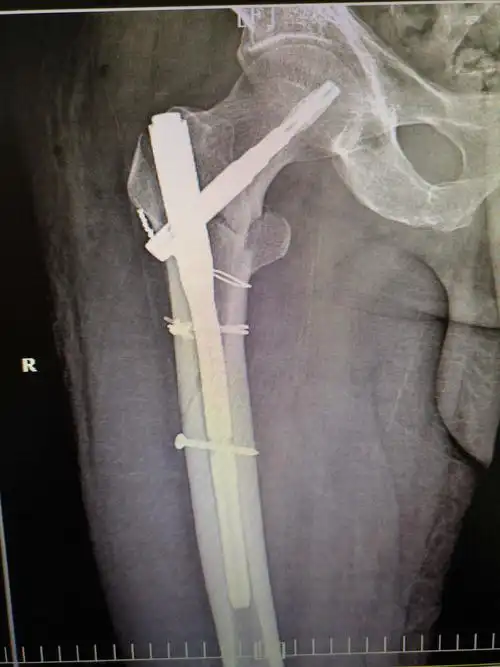

股骨骨折

右大腿着力,伤右髋部剧烈疼痛,活动受限,拍片示右股骨近端粉碎性骨折

钛缆 pfna治疗老年股骨近端粉碎性骨折